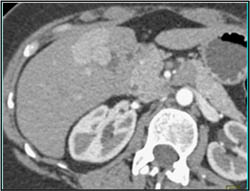

Focal Nodular Hyperplasia (FNH)